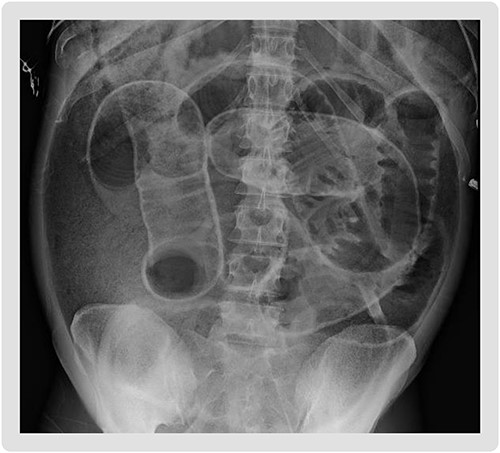

The patient is a 36-year-old female with a history of chronic constipation and toxic megacolon who presented in septic shock with severe abdominal distention and peritonitis. During the patient’s prior hospitalization, she presented with nausea, vomiting and abdominal distention. Computed tomography (CT) scan was performed and revealed stool in the colon without any obvious obstruction. She was diagnosed with chronic constipation with retained stool and thus underwent multiple fecal disimpactions during that hospitalization. The patient was seen by a gastroenterologist during the admission, who recommended colonoscopy as an outpatient. She would require further diagnostic work-up including Sitz marker study to diagnose possible colonic inertia [5]. The patient eventually had restoration of bowel function with laxatives after hospitalization Day 4 and was subsequently discharged. She continued to take her laxative for bowel movements, however, experienced no bowel movement for 7 days and had progressively worsening distension. She then presented to the hospital after developing sudden abdominal pain which prompted her to seek medical evaluation. On presentation, the patient was tachypneic, tachycardic and hypotensive. A stat abdominal X-ray demonstrated pneumoperitoneum, increasing urgency for the patient’s definitive surgical management (Fig. 1).

Supine abdominal plain film on admission demonstrating Rigler’s sign, bowel loops outlined by air, increasing suspicion for large volume pneumoperitoneum.